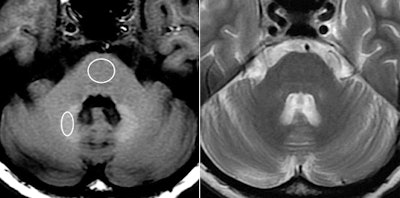

MRI of a 45-year-old woman with glioblastoma treated with surgery, chemotherapy, and radiation therapy. Unenhanced T1-weighted image (above, left) shows high-signal-intensity globus pallidus. Fast spin-echo T2-weighted image (above, right) at same level. Unenhanced T1-weighted image (below, left) shows high-signal-intensity dentate nucleus. Fast spin-echo T2-weighted image (below, right) at same level. Images courtesy of Radiology.

The analysis showed a significant correlation between the number of previous contrast administrations and signal intensity in the dentate nucleus and the globus pallidus, according to the researchers. Hyperintensity was significantly greater in patients who had received contrast, compared with those who received unenhanced scans.

Increased signal intensity in the dentate nucleus and globus pallidus on unenhanced MRI may be due to the number of previous gadolinium-based contrast administrations, Kanda and colleagues noted.